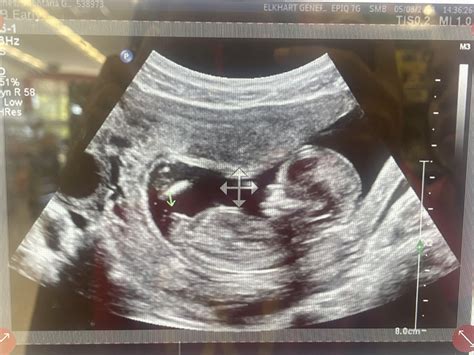

14 Week Ultrasound

A 14 week ultrasound is typically performed between 13 weeks and 14 weeks of pregnancy. It is often referred to as the “nuchal translucency” scan because it measures the thickness of fluid behind the baby’s neck. This measurement, along with other factors, can help assess the risk of certain chromosomal abnormalities, such as Down syndrome.

During the 14 week ultrasound, you will lie on an examination table with your abdomen exposed. The technician will apply a gel to your belly and use a transducer to capture images of your baby. The procedure is painless and usually takes about 20-30 minutes.

The technician will look for several key features, including:

• Baby’s Heartbeat: The heartbeat should be clearly visible and audible.

• Nuchal Translucency: The thickness of the fluid behind the baby’s neck will be measured.

• Baby’s Anatomy: The technician will check for the presence of all major organs and structures.

• Placenta and Amniotic Fluid: The position of the placenta and the amount of amniotic fluid will be assessed.